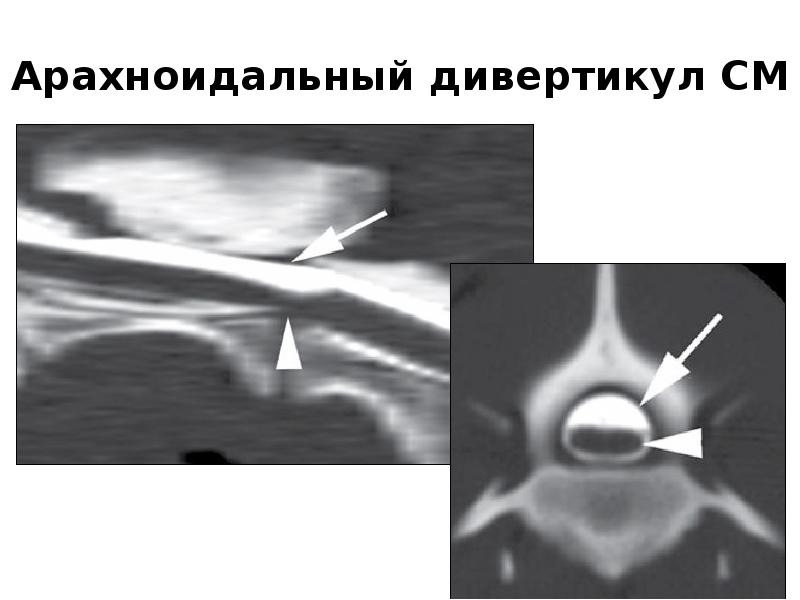

Компьютерная томография в неврологии презентация - 86 фото